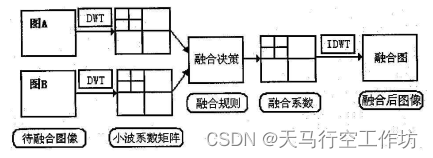

图像融合框架如下图所示,

首先将图像分别进行小波变换,即利用小波金字塔算法将空间域上已经配准止之后的两幅图像分别变换到小波域;其次,根据需要选择不同的融合规则,常见的图像融合方法有加权平均法、局部方差法、局部能量法、PCA方法等等。最后根据融合规则分别将不同金字塔的小波图像进行融合,再利用逆变换将其变换回空域即可实现CT图和MRI的图像融合。